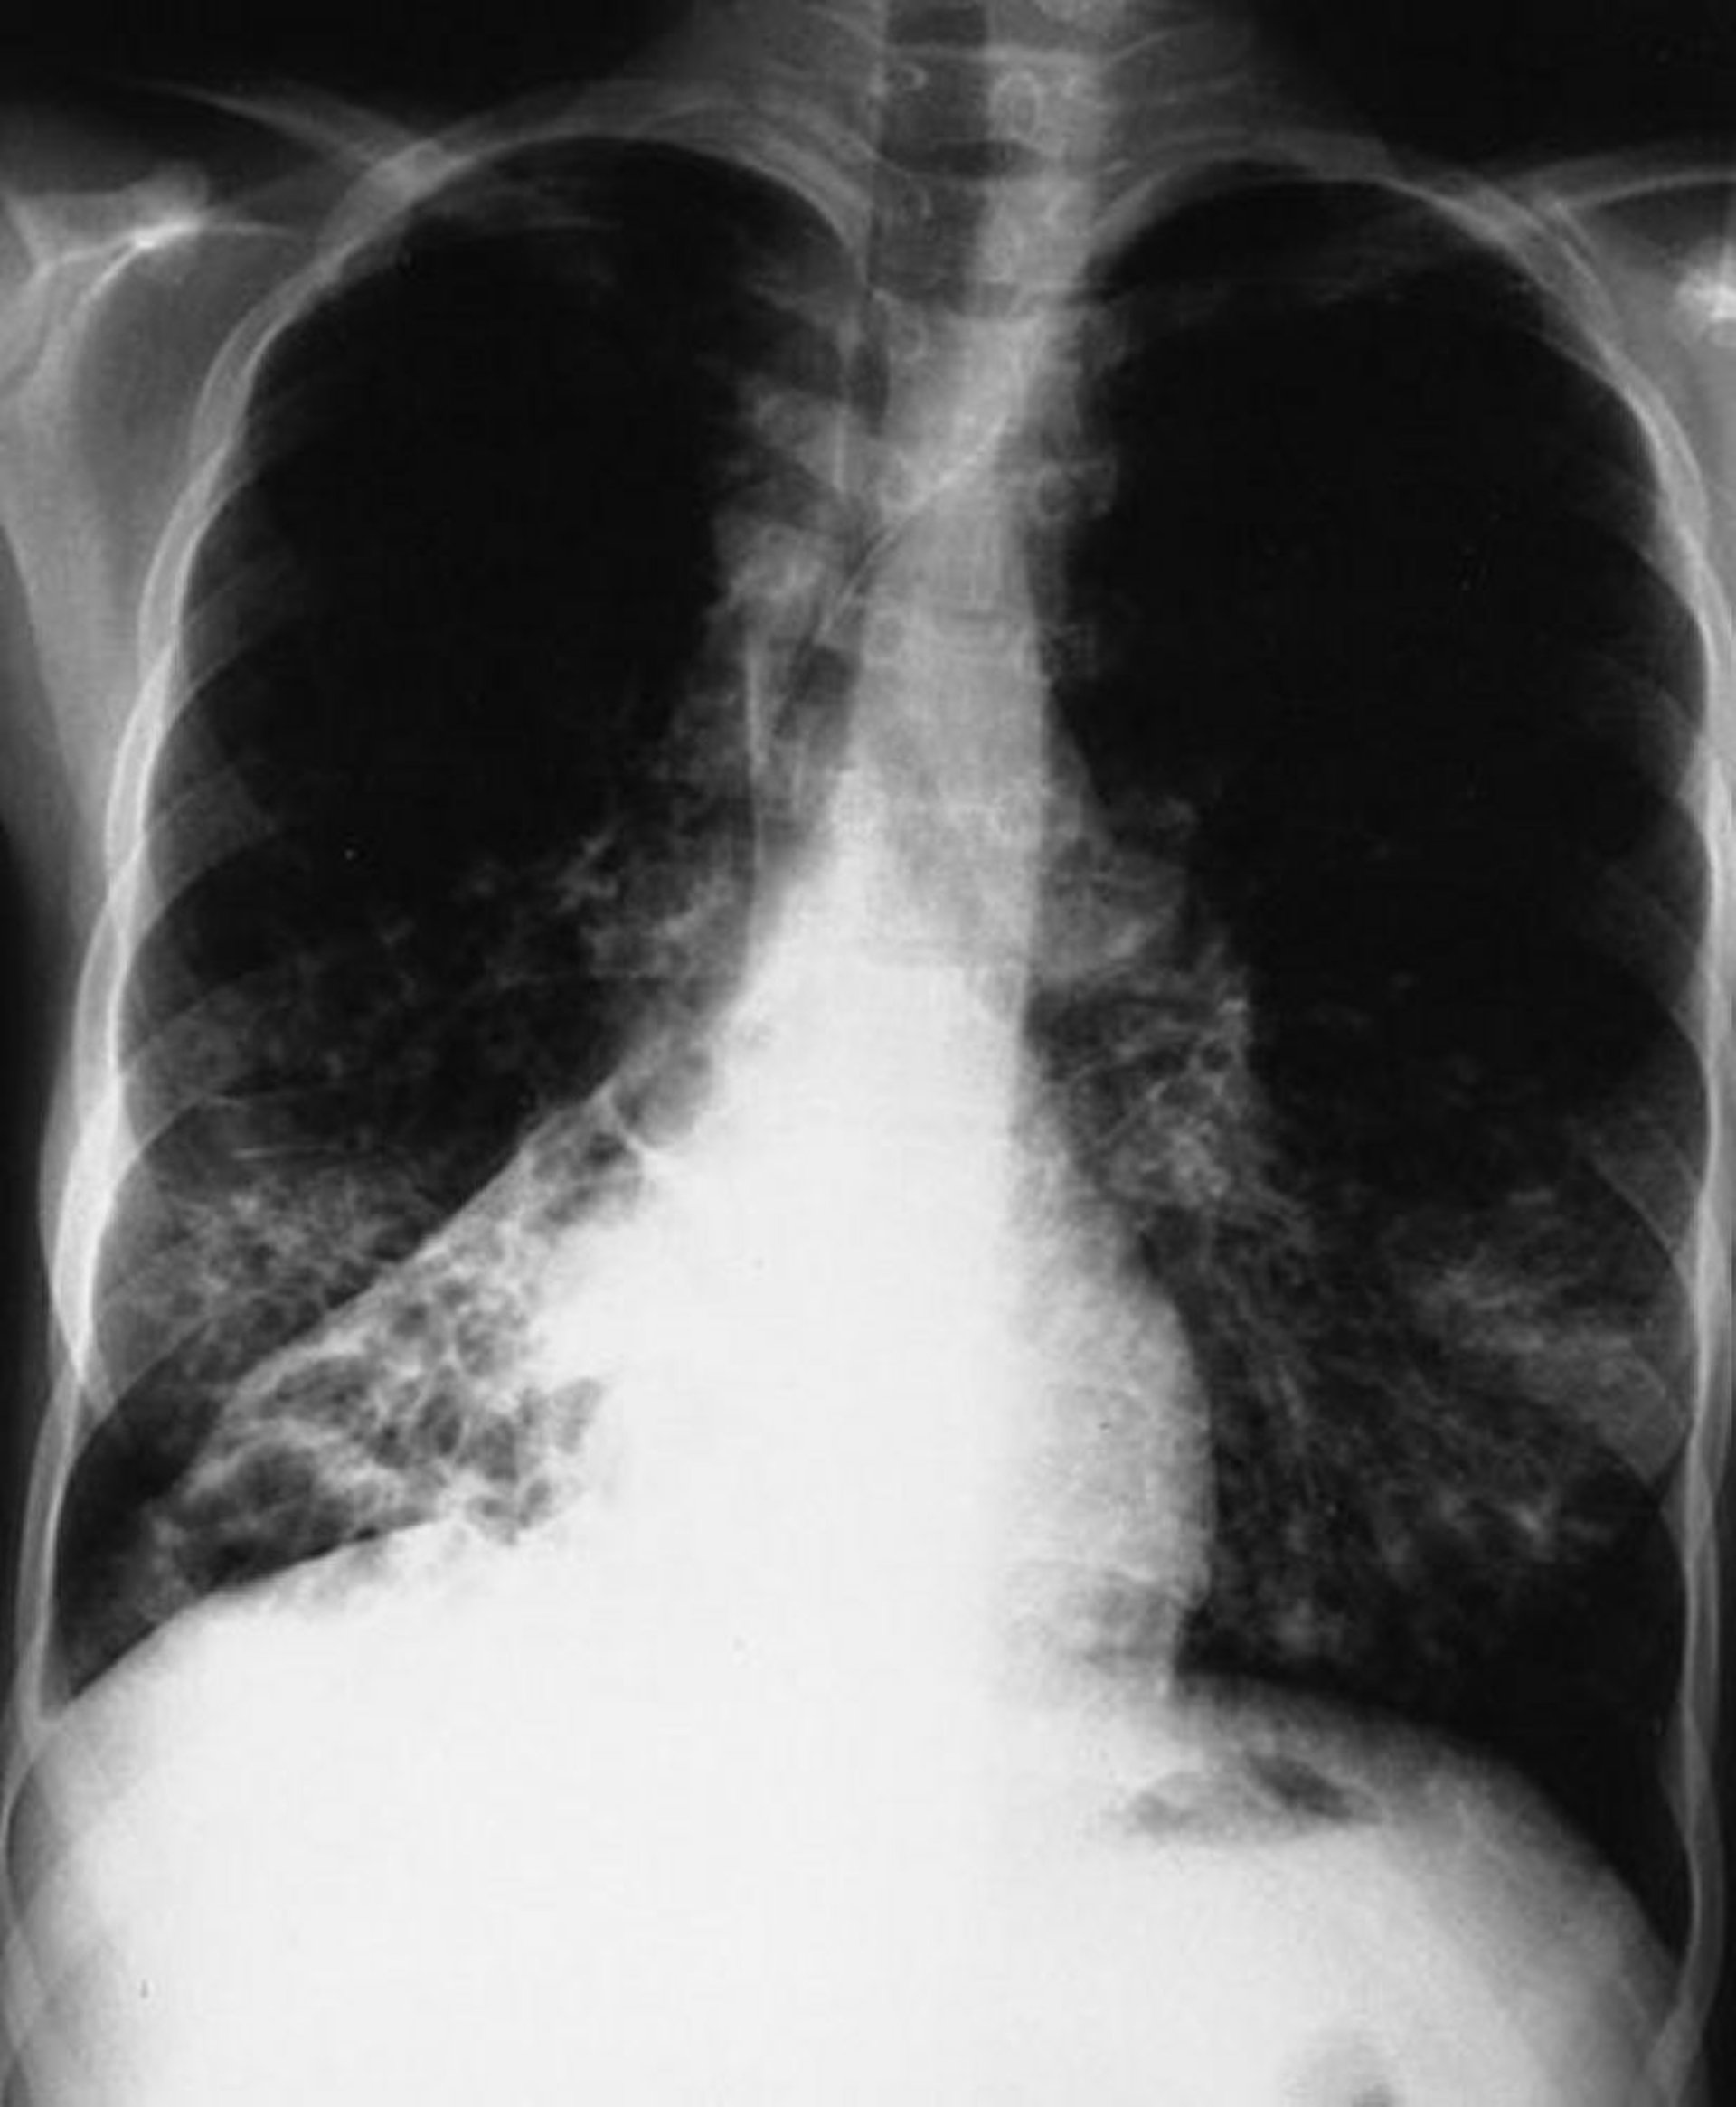

Fibrosis quística (radiografía de tórax)

Esta radiografía de tórax muestra un colapso del lóbulo inferior derecho. Los hallazgos son típicos de la fibrosis quística, pero no son específicos.

By permission of the publisher. From Berman L: Atlas of Anesthesia: Critical Care. Edited by R Miller (series editor) and RR Kirby. Philadelphia, Current Medicine, 1997.